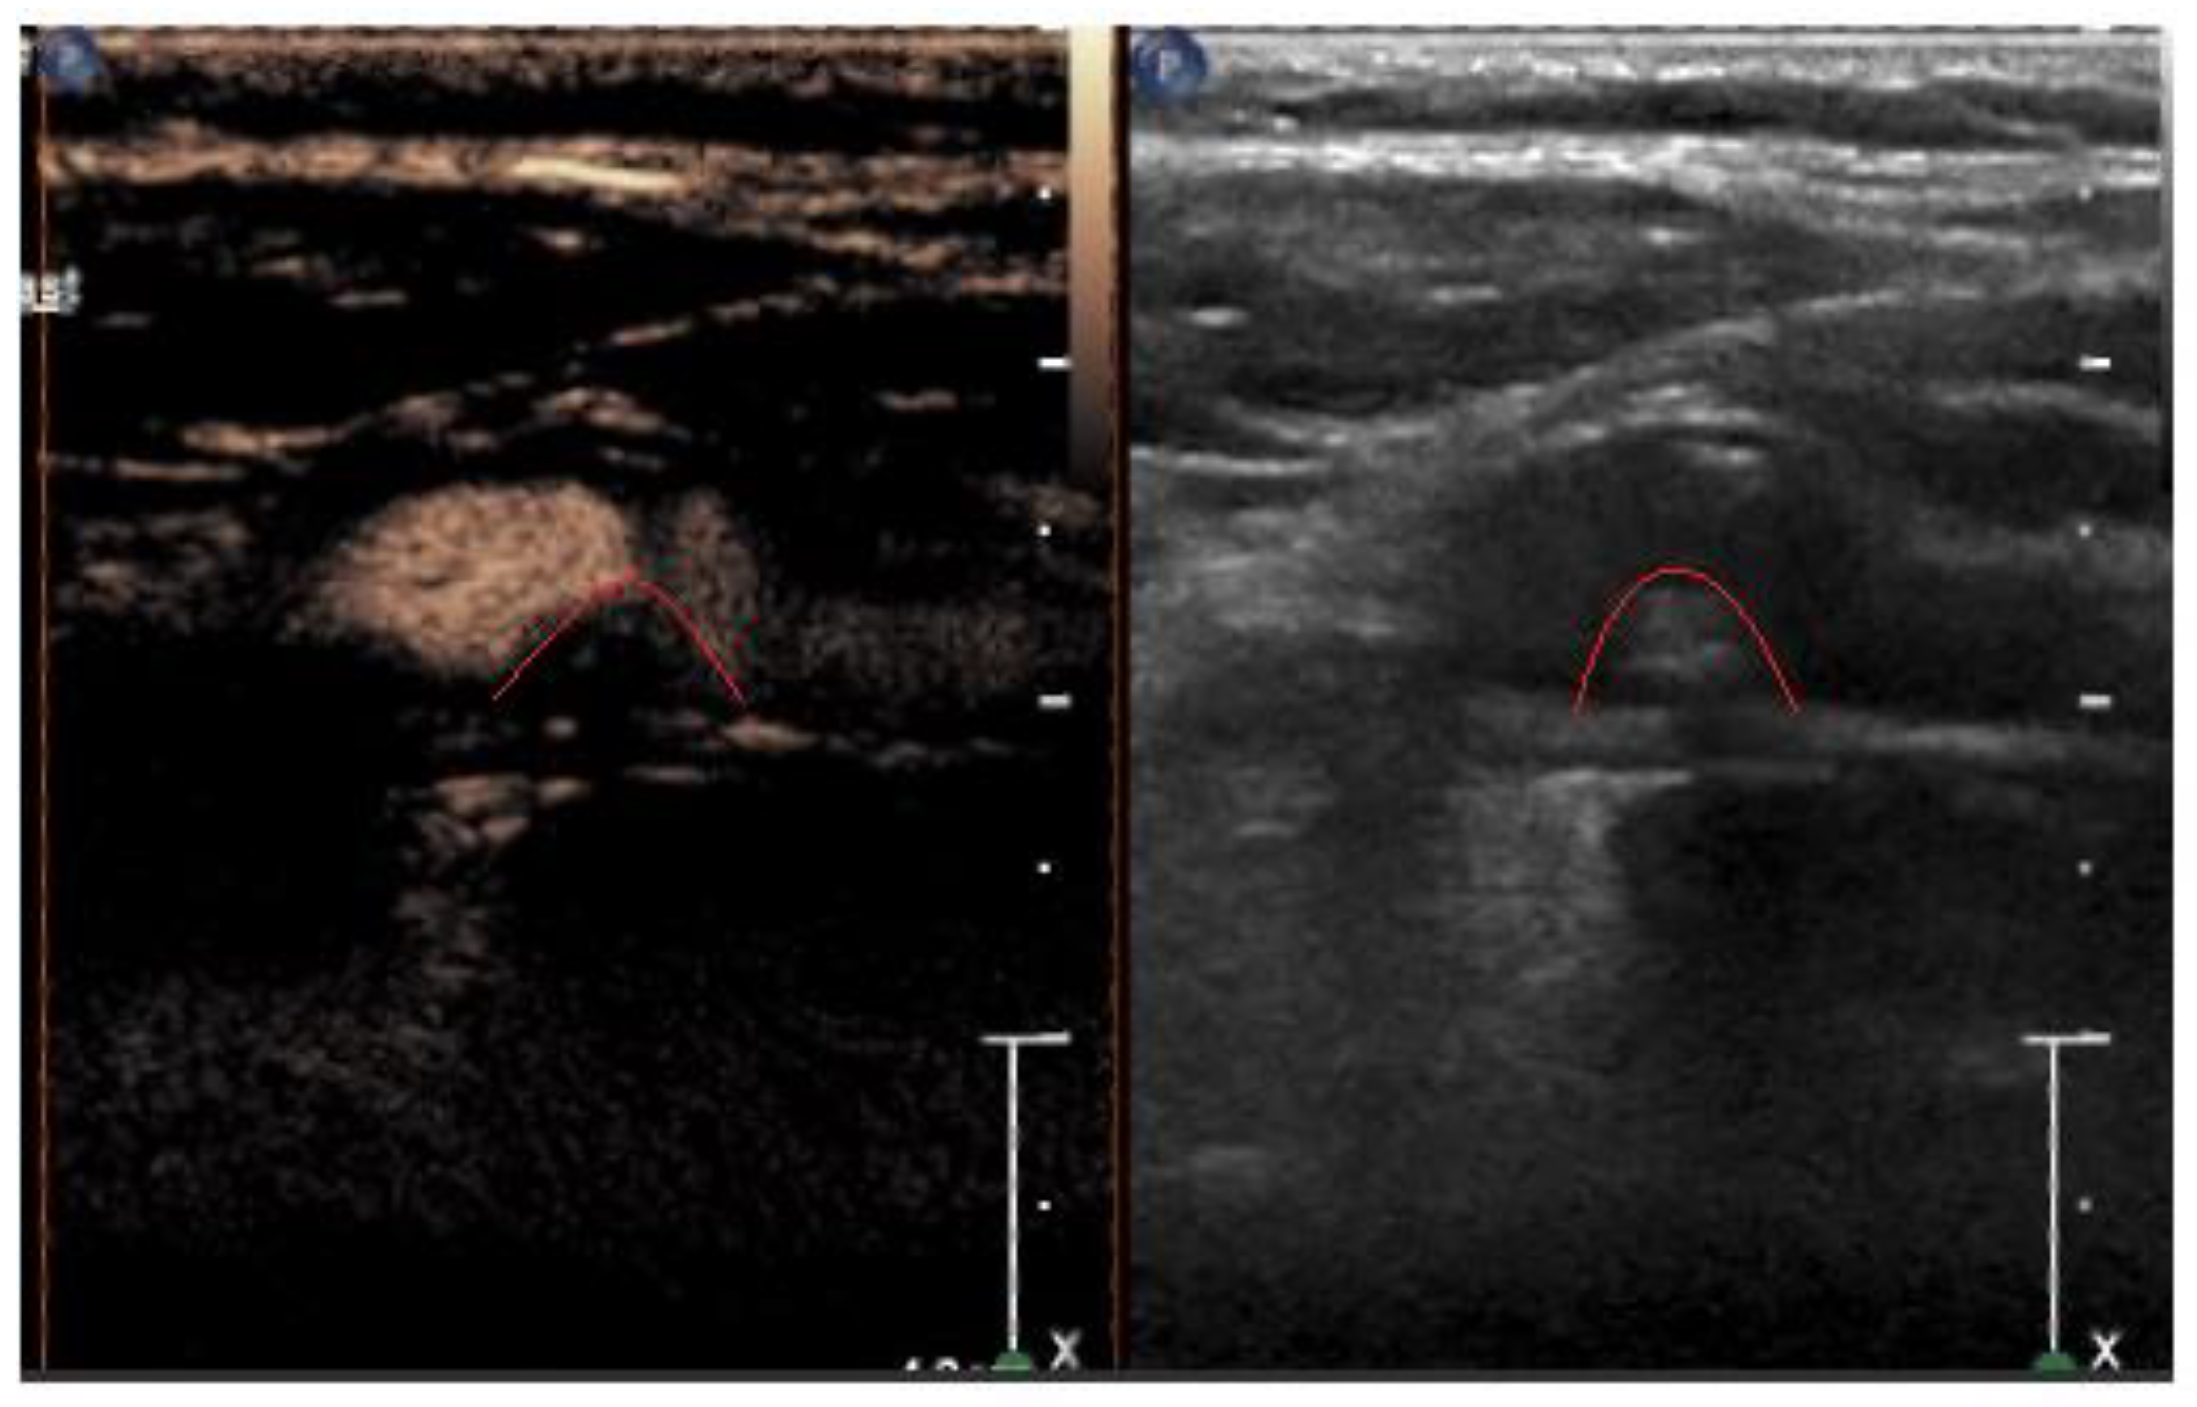

2.2. Ultrasound Characteristics

2.3. Ultrasound Contrast Agent

2.4. Principles of Contrast Ultrasound Based on Contrast Agent Pharmacokinetics